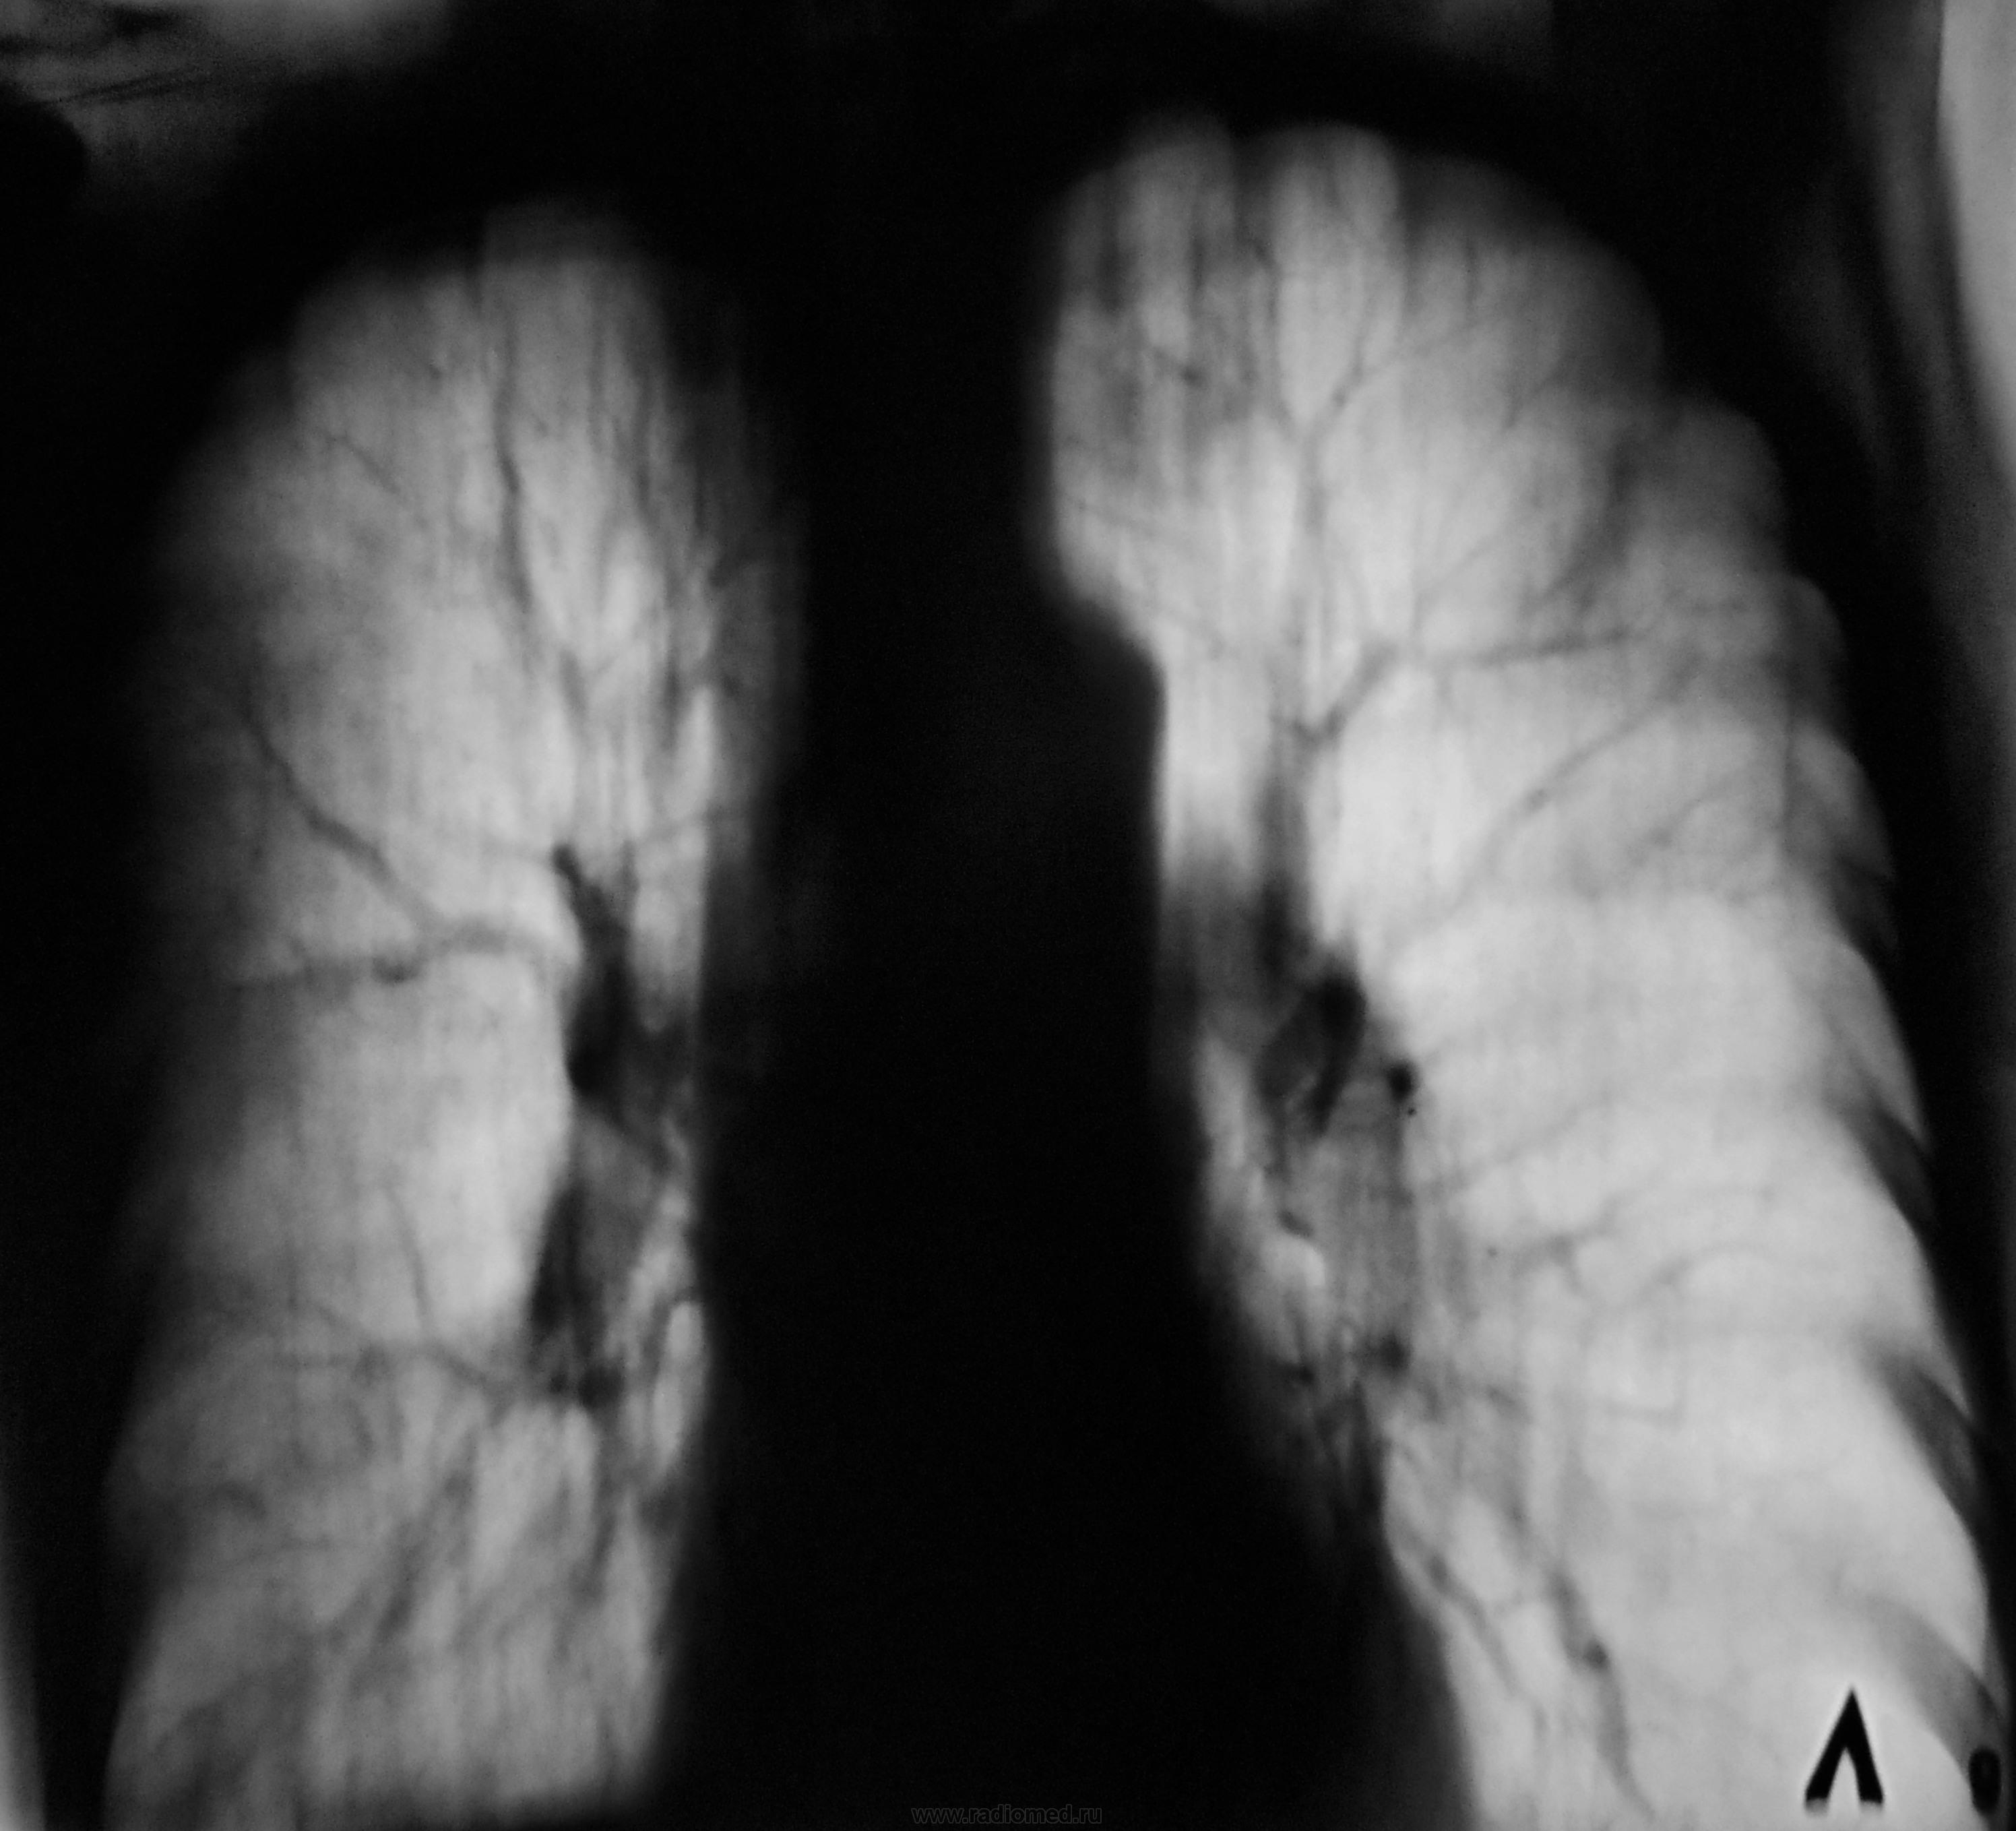

Срезы близки к срединному, а какой из них вентральный, какой дорзальный - не угадаю. Если первая пара "выше" второй, то я бы подумал на размазанное сочленение 1-го левого ребра с грудиной - мне кажется, он более кальцинирован.

Снимок №2 - более дорзальный (предположу 9-10 см), №3 - его обработка, №4 - более вентральный срез, №5 - его обработка. Валентин Львович, отчего же Вы брезгуете указать см на снимках. S1-2 слева и S10 справа кажутся "заплеванными". Синус справа облитерирован. Корни уплотнены. Эмфизема хороша. Плевро-перикардиальные спайки слева.